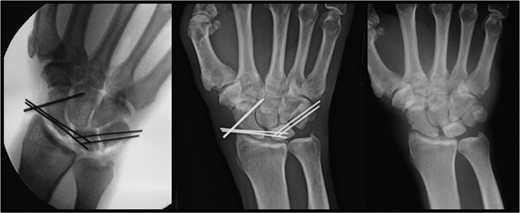

After stabilization, open reduction of the perilunate dislocation with a carpal tunnel release was performed through a combined volar and dorsal approach 12 h after presentation (Fig. 2). The lunate had no ligamentous attachments and was free floating in the distal forearm. The scapholunate and lunotriquetral ligaments were completely avulsed and irreparable. Reduction was achieved with manipulation using a joystick technique with K-wires placed into the scaphoid and lunate. K-wires were placed through the scaphocapitate, scapholunate and lunotriquetral intervals (Fig. 3). The CMC subluxations were stable when stressed under fluoroscopy, establishing the chronicity of these injuries.

Left: intraoperative image demonstrating K-wires supporting the lunate. Center: postoperative image at 10 months demonstrating the lunate still in proper position with retained hardware. Right: postoperative image at 10 months demonstrating proper positioning of the lunate after removal of hardware.

Postoperative examination revealed a neurovascularly intact right upper extremity. The patient was lost to follow-up until presenting with symptomatic instrumentation 10 months postoperatively. Normal lunate radiographic density on X-rays confirmed revascularization of the lunate (Fig. 3). Clinical evaluation demonstrated a neurovascularly intact, stable carpus without evidence of carpal collapse or arthrosis (Fig. 3). The instrumentation was removed and the patient reported no pain with daily activities and full range of motion when compared with the uninjured left hand.